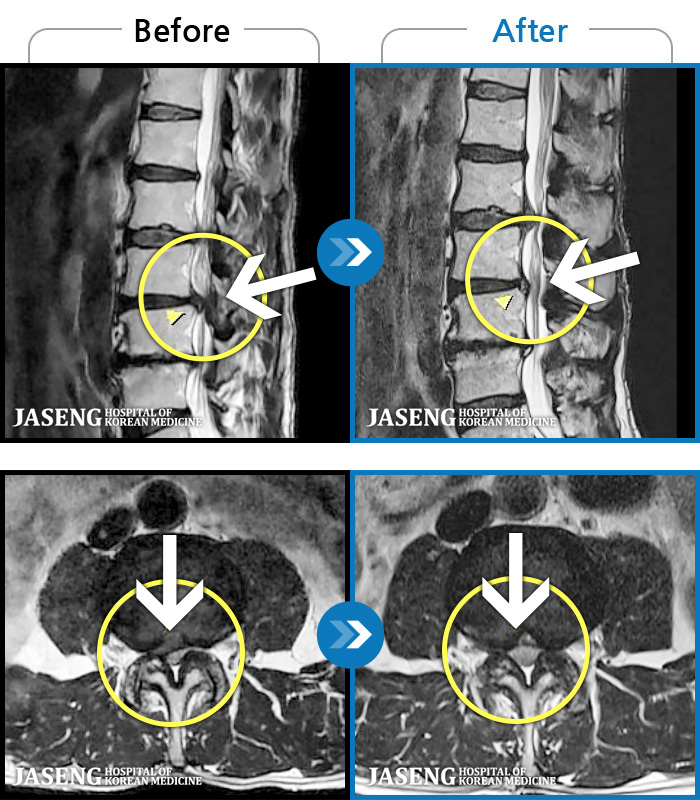

MRI ũ ʸ Ȯϼ.